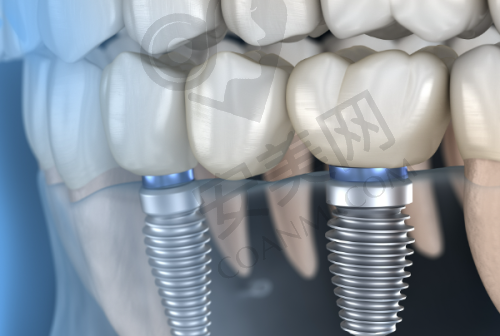

做完CT检查后,医生根据我的口腔检查结果和CT影像,为我制定了个性化的种植方案。医生向我详细地介绍了种植方案的内容,包括种植体的选择、种植的位置和数量等。他告诉我,根据我的牙槽骨情况,选择了适合我的种植体品牌和型号,这种种植体具有良好的生物相容性和稳定性,能够更好地与牙槽骨结合。同时,医生还考虑到了我的美观和功能需求,对种植的位置和角度进行了严谨的设计。在制定方案的过程中,医生还耐心地解答了我提出的各种疑问,让我对种植方案有了充分的了解和信心。

确定好种植方案后,医生就安排我进行种植牙手术。在手术前,护士为我进行了口腔消毒和局部麻醉。麻醉生效后,我并没有感觉到明显的疼痛。手术过程中,医生和护士都非常专精和细心,他们密切配合,操作熟练。我能感觉到医生在小心翼翼地进行每一个步骤,虽然我有些紧张,但医生时不时地跟我交流,安慰我,让我放松了不少。整个手术过程大约持续了一个多小时,手术非常顺利。术后,医生向我交代了一些注意事项,比如要注意口腔卫生,避免食用实力强的食物等。

杭州瑞创口腔医院的种植牙技术有特别多特色。首先,医院采用了数字化种植技术,通过口腔CT和计算机辅助设计,能够更严谨地规划种植位置和角度,提高种植的成功几率。其次,医院拥有多种品牌和型号的种植体可供选择,医生会根据患者的具体情况,为患者推荐更适合的种植体,确保种植成效和使用寿命。此外,医院的医生团队经验多,他们在种植牙领域有着深厚的造诣,能够为患者提供个性化的治疗方案。而且医院的服务也非常贴心,从就诊前的询问到术后的回访,每一个环节都让患者感受到了关怀和温暖。